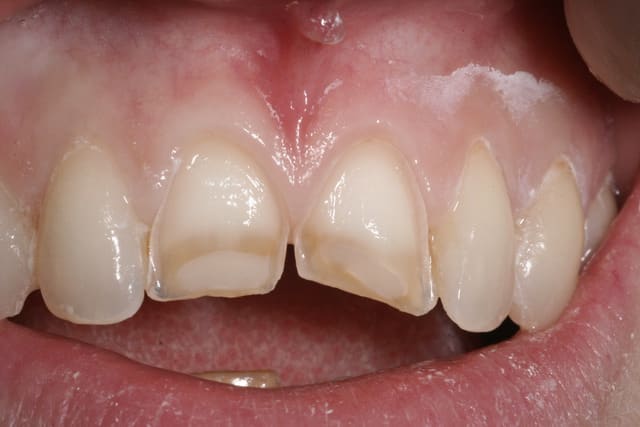

un petit cas recent de 22 en grain de riz...